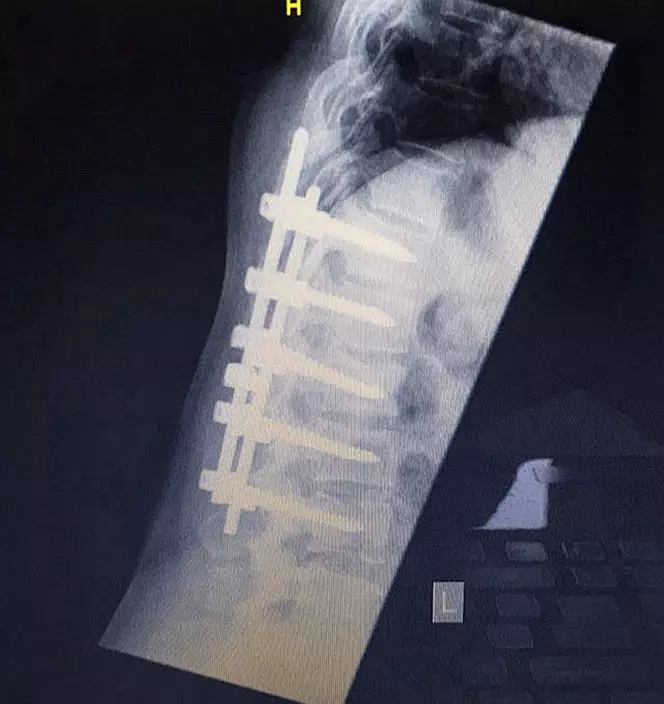

After being flown by helicopter to Southmead Hospital in Bristol, Sallyanne, who had smashed five vertebrae, underwent a nine-hour operation to reconstruct her shattered back.

X-ray of Sallyanne's back following her operation (1)(PA Photo)